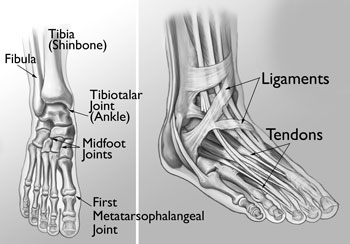

(Left) The joints of the ankle, midfoot, and big toe are commonly affected by arthritis. (Right) Ligaments and tendons connect the bones to each other and to the surrounding muscles of the lower leg.

Reproduced and modified from The Body Almanac. © American Academy of Orthopaedic Surgeons, 2003.

AnatomyDuring standing, walking, and running, the foot and ankle provide support, shock absorption, balance, and several other functions that are essential for motion. Three bones make up the ankle joint, primarily enabling up and down movement. There are 28 bones in the foot, and more than 30 joints that allow for a wide range of movement.

In many of these joints the ends of the bones are covered with articular cartilage—a slippery substance that helps the bones glide smoothly over each other during movement. Joints are surrounded by a thin lining called the synovium. The synovium produces a fluid that lubricates the cartilage and reduces friction.

Tough bands of tissue, called ligaments, connect the bones and keep the joints in place. Muscles and tendons also support the joints and provide the strength to make them move.